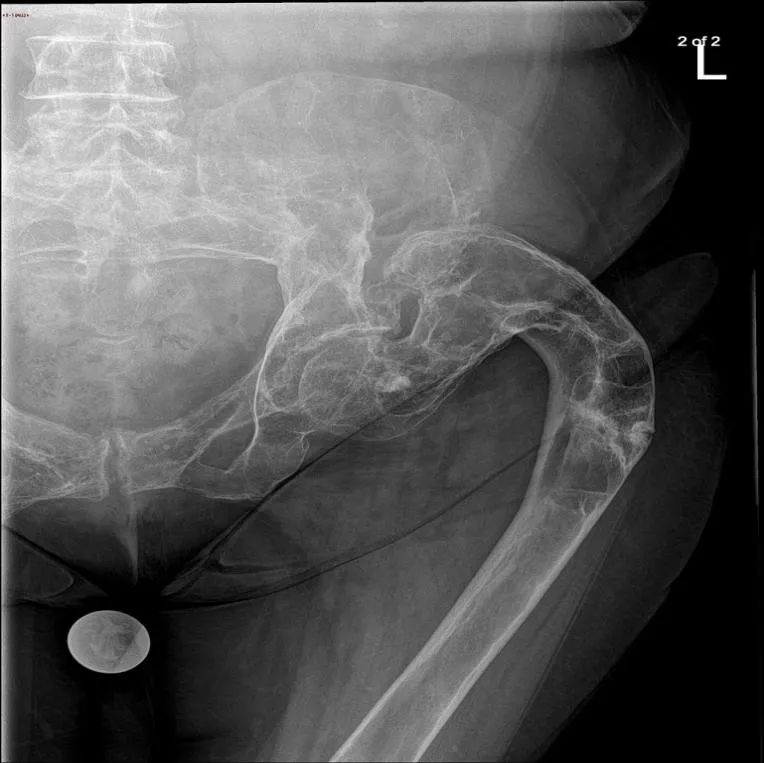

(注:左侧股骨上段骨质呈 「 牧羊人拐杖 」 样改变,见囊状膨胀性透光区,边缘见硬化边,临近骨皮质变薄,病变范围较局限,伴左侧股骨上段畸形。)

(注:枕骨斜坡偏左份骨质呈膨胀性、磨玻璃样密度增高影改变,边界较清,临近骨皮质变薄,未见明显骨膜反应。)